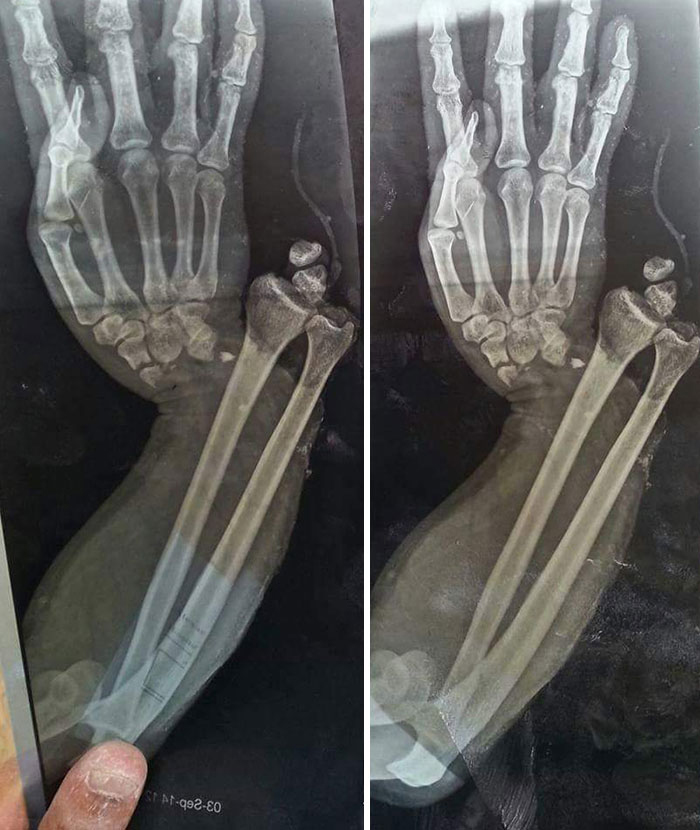

Ну, это отстой...